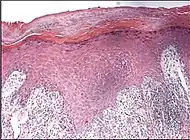

Spongiotic dermatitis

It is characterized by epithelial intercellular edema.[2]

| Generally/Not otherwise specified[notes 2] | Typical findings:[2]

|

Typical findings:[2]

|

Typical findings:[2]

PAS stain is essential to exclude fungal infection.[2] |

Subacute Subacute |

|

| Allergic/contact dermatitis or atopic dermatitis | As above. Eosinophils may be present in the dermis and epidermis (eosinophilic spongiosis).[2] |  Allergic dermatitis Allergic dermatitis |

.jpg.webp) Atopic dermatitis Atopic dermatitis | ||

| Seborrheic dermatitis | Typical findings:[5]

|

Typical findings:[5]

|

Typical findings:[5]

|

| |

In addition to above, an unspecific spongiotic dermatitis can be consistent with nummular dermatitis, dyshidrotic dermatitis, Id reaction, dermatophytosis, miliaria, Gianotti-Crosti syndrome and pityriasis rosea.[2][notes 2]